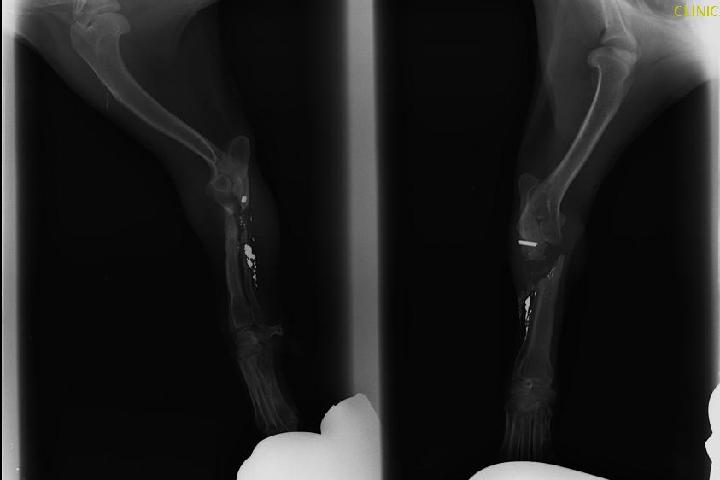

Zoe es un perrito cruce de picher que hace dos años apareció con una bala del 22 en la pata delantera derecha, le operaron pero no quedó bien, su mano baila cuando anda, tiene que ir a saltitos, tenía demasiada infección, ahora tiene una nueva oportunidad de que le operen y que su manita deje de bailar, la operaciòn es larga, complicada y costosa, él se merece esta oportunidad, cada vez que quiere jugar o correr se desnivela y cae. Es una pena verse así, con lo alegre que es. Muchas gracias

Zoe es un perrito cruce de picher que hace dos años apareció con una bala del 22 en la pata delantera derecha, le operaron pero no quedó bien, su mano baila cuando anda, tiene que ir a saltitos, tenía demasiada infección, ahora tiene una nueva oportunidad de que le operen y que su manita deje de bailar, la operaciòn es larga, complicada y costosa, él se merece esta oportunidad, cada vez que quiere jugar o correr se desnivela y cae. Es una pena verle así, con lo alegre que es. Muchas gracias